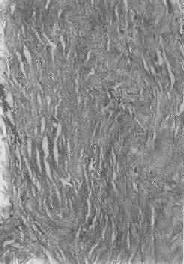

图1-19 纤维瘢痕组织的玻璃样变

胶原纤维变粗,互相融合呈均质梁状